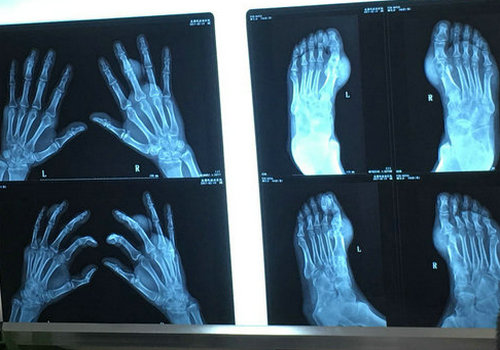

右手第3指近节指骨远端骨皮质毛糙不整,余双手各骨骨质未见确切增生、双手及破坏征象,双手各指间关节间隙变窄,双手多发痛风石形成,余未见特殊改变。

双足第1跖趾关节均可见穿凿样骨质破坏,破坏区边缘骨皮质翘起,双第1跖趾关节周围均可见不规则较大较软组织肿块影,余未见特殊改变。

1、双手痛风性关节炎伴多发痛风石形成。

2、双足痛风性关节炎伴第1跖趾关节痛风石形成。

3、双足第1跖趾关节关节骨质呈穿凿样骨质破坏。

4、右侧肘关节痛风性关节炎伴痛风石形成。